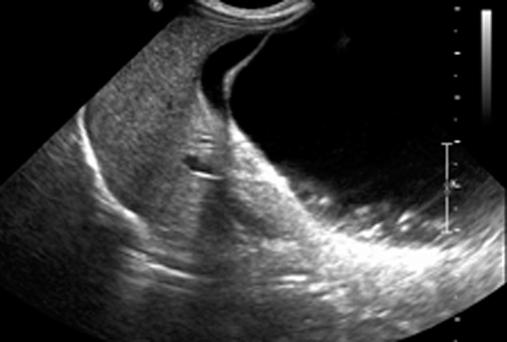

Benign congenital liver cysts are rare in the pediatric population and often present a challenge in the diagnosis. Therefore, with recent advances in the field of minimally invasive surgery, this technique may be ideal in achieving both diagnosis and curative resection. We describe the case of a 2-month-old female initially referred for an antenatal ultrasound in the third trimester revealing a 7-cm intraabdominal cystic lesion of unknown origin. She was found to have a 10-cm hepatic cyst successfully treated by laparoscopic surgery. Our approach consisted of complete cyst excision along with its attached hepatic parenchyma. We recommend this technique as safe and feasible.